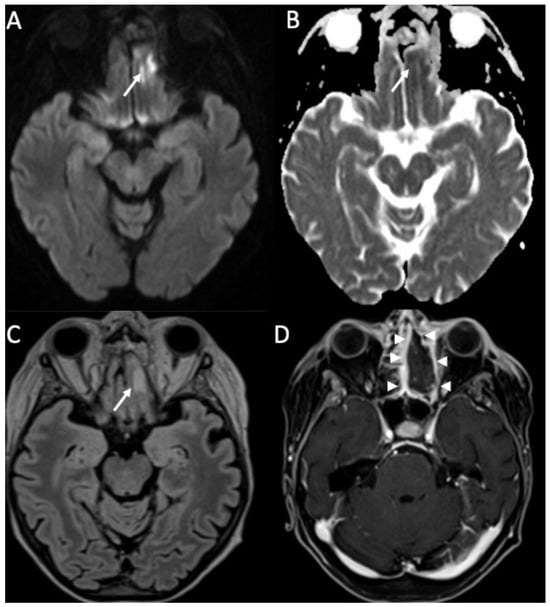

| Piogenic Meningitis | • Cerebrospinal fluid hyperintensity in T1 and FLAIR • Restricted diffusion of the subarachnoid spaces • Meningeal enhancement on T1 and FLAIR |

| Tuberculosis | • Leptomeningeal enhancement in the basal cisterns • Hydrocephalus very common • Infarcts in the basal ganglia due to vasculitis • Possible concomitant tuberculomas or miliary tuberculosis |

| Herpes Virus type 1 | • Mesio-temporal involvement • Bilateral and asymmetric pattern • Cortical hyperintensity on T2 and FLAIR, with restricted diffusion (acute phase) and cortical enhancement (subacute phase) • Hemorrhagic foci |